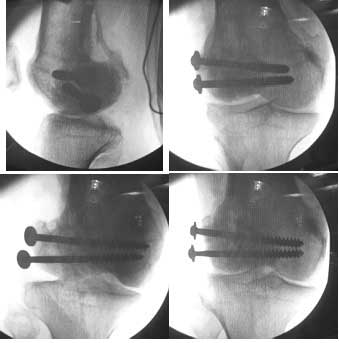

I opened it up from the lateral aspect.

Freed up the non-union site with minimal disturbance to the posterior and lateral soft tissue attachments on the lateral condyle fragment.

Applied a distractor between femoral shaft and tibia, to create a space on the lateral aspect.

This brought the lateral condylar fragment into a position that seemed to be reasonably well aligned, but showed up a bone gap.

This was fixed temporarily, bone grafted with tricortical struts, and fixed by two cancellous screws. The fragment was not large enough to afford any fixation to a plate or such implant, and the screws held it compressed well to the rest of the distal femur.

Pictures attached.